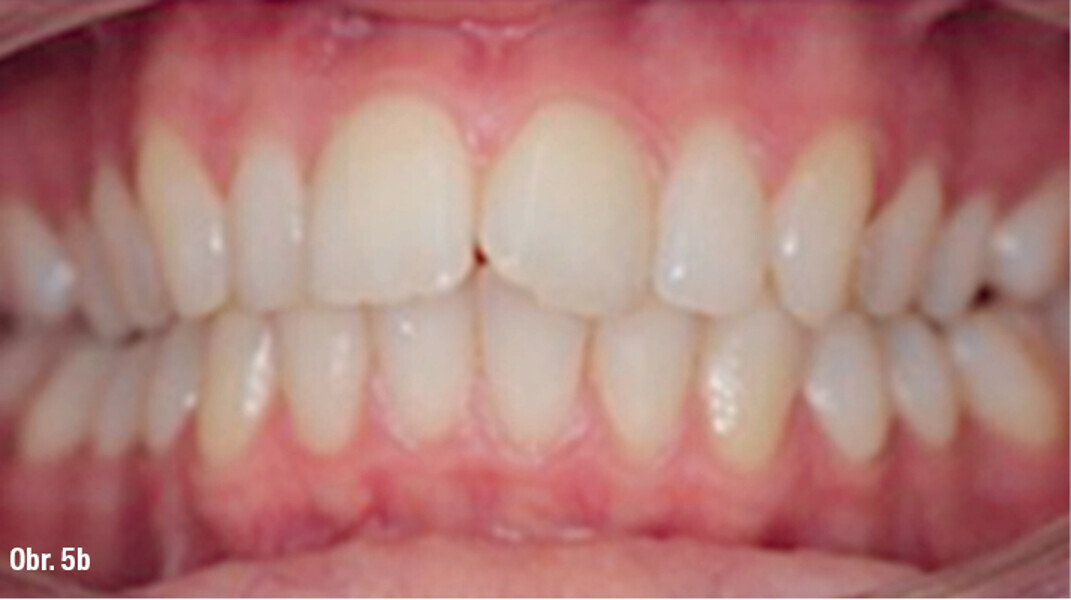

Distalizace horních molárů pomocí alignerů a cyklických sil